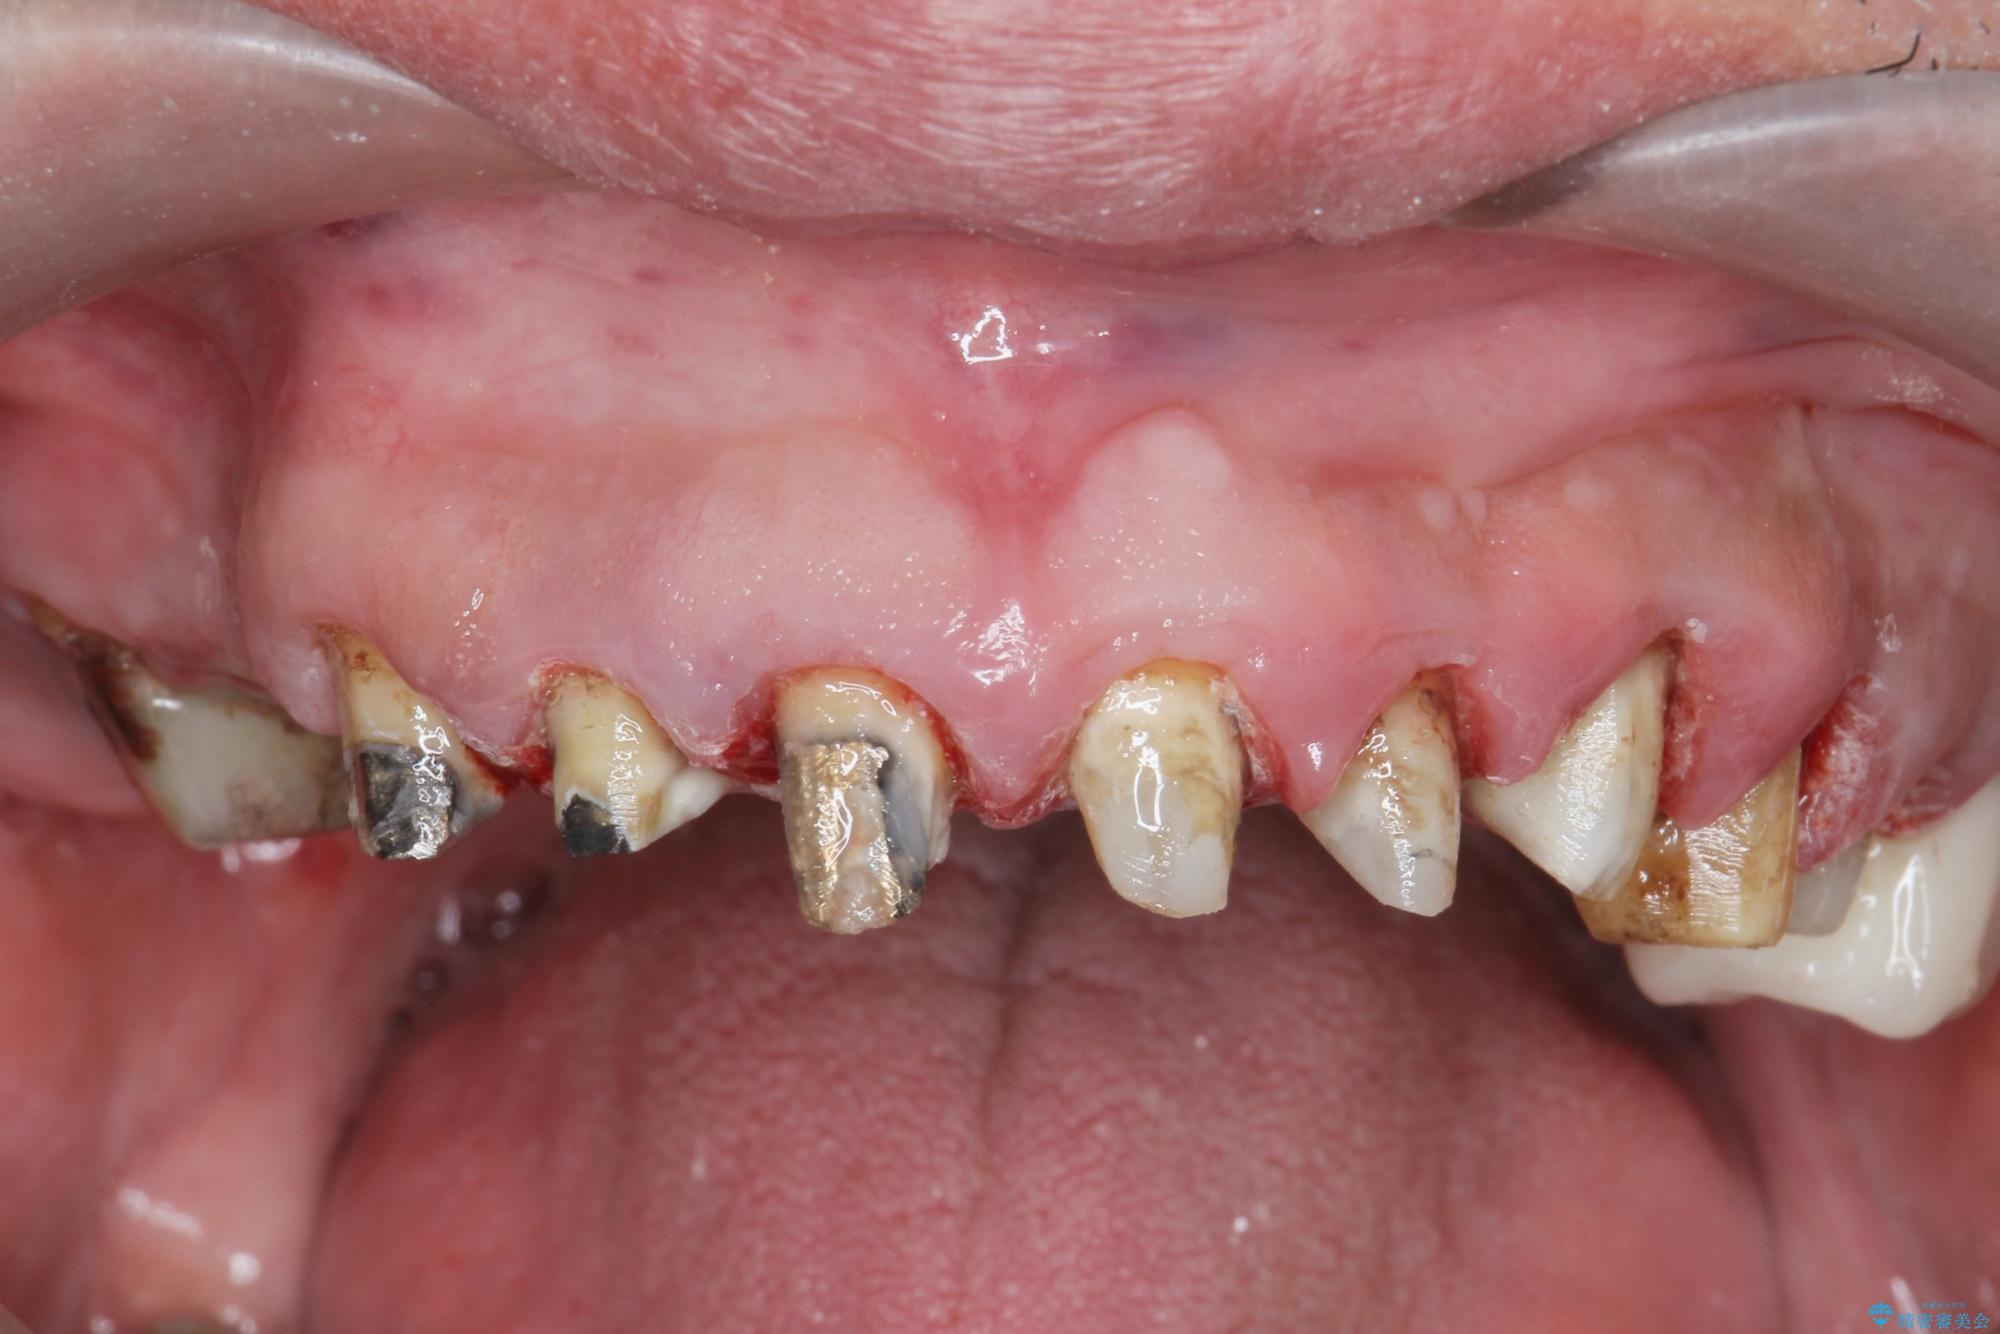

[ 歯周外科手術 ] セラミック治療後の歯ぐきの違和感

歯周組織検査を行うと歯ぐきからは容易に出血し、X線検査より歯とセラミッククラウンの適合が悪い(ピッタリと合っていない)状態が示唆され、歯ぐきの炎症を惹起している状態でした。

セラミッククラウンを除去し仮歯を装着し、歯周外科手術を行い歯ぐきの状態を改善したのち、適合の良いセラミッククラウンを再作製をする治療計画としました。